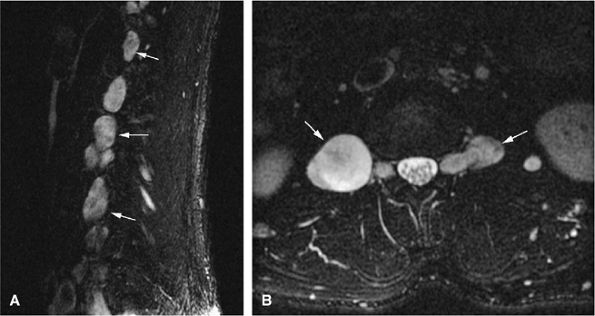

![]() |

-

The expansile lesion may have internal septations, fluid–fluid levels, and areas of bright signal intensity on both T1- and T2-weighted images, depending on the chronicity of the associated hemorrhage (Figs. 14-52 and 14-53).77

The fluid–fluid level probably represents layering of uncoagulated blood within the lesion.78 On T1-weighted images, increased signal intensity in the gravity-dependent layer represents methemoglobin. It may be difficult to exclude the possibility of malignancy when severe inhomogeneity of signal intensity is observed.